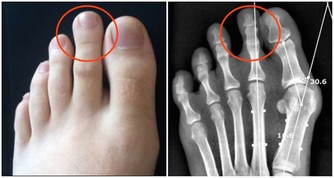

而尿騷味,則通常提示腎有問題了。

人體腎臟具有強大的代償功能,只要腎功能喪失不超過75%,仍能保持人體內環境的穩定。

所以,慢性腎衰病人早期常無明顯臨床症狀,往往容易誤診、漏診,使腎衰病人失去最佳的治療時機。

食慾減退和晨起噁心、嘔吐等,是慢性腎衰常見的早期表現。

另外,一些慢性腎衰病人還有一些特殊的臨床表現,如口腔內有氨的氣味,也就是你說的尿味,尿毒症病人更為明顯。

主要原因是,隨著腎功能的減退,腎臟的溶質清除率下降和某些肽類激素的滅活減少,造成多種毒素在血液和組織中蓄積,最常見的毒素就是尿素等。

在口腔中,因為唾液中的尿素被分解為氨,故病人呼出的氣體有尿味。

這種氣味的濃淡隨病情的進退而變化,在病情好轉時,口中尿味淡些,病情加重時尿味變濃。